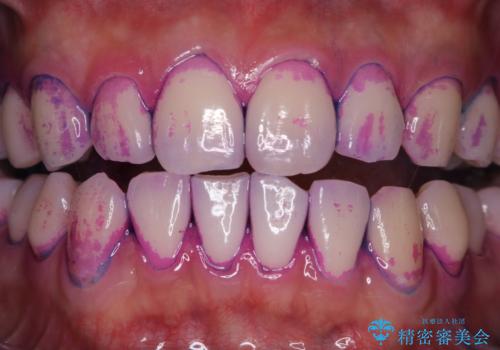

歯垢染色液を使うと、一見きれいな歯でも染まっている所が全て歯垢(プラーク)なのがはっきり分かります。歯に付着した歯垢(プラーク)は肉眼では認識しにくいものです。完璧に磨けているつもりでも、磨き残しが残っているかもしれません。